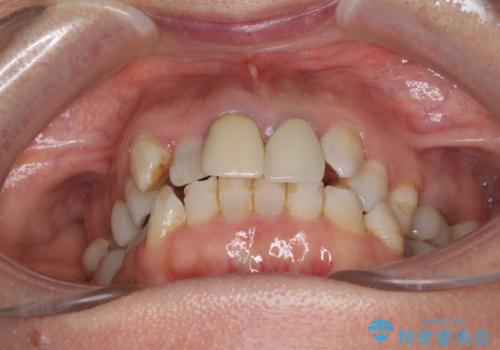

- 全顎的な歯列不正と、銀歯だらけの奥歯を気にして来院された患者様です。

奥歯の銀歯は、セラミッククラウンを装着するには歯の高さが不十分であり、そのままでは矯正治療を行うことが困難であるため、歯冠長延長術を行うこととしました。

また、根管治療の必要な歯がいくつかあるため、歯周外科治療の治癒期間を利用して根管治療を行い、その後インビザラインにて矯正治療を行うこととしました。

矯正治療後にはオールセラミッククラウンにて補綴治療を行うこととしました。